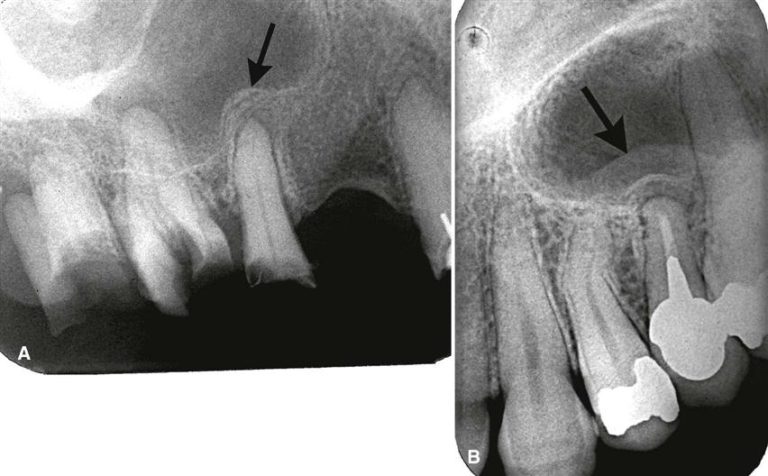

Анатомия: Межкорневая костная перегородка

Раздел: Галерея впечатлений